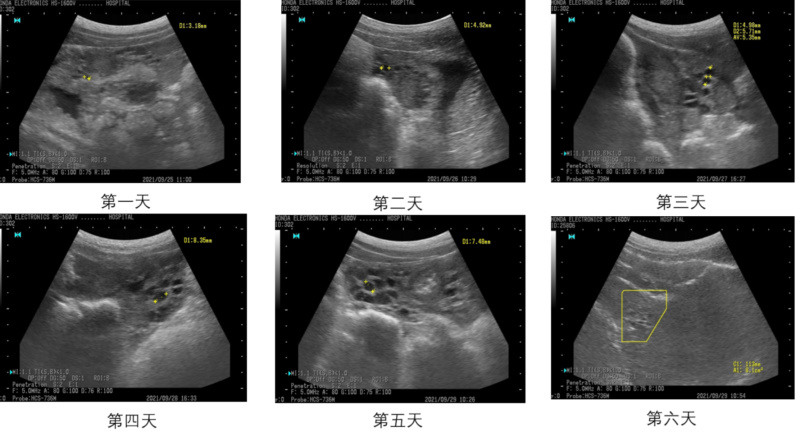

母猪断奶后6天卵泡发育变化